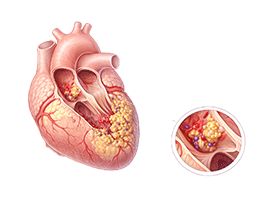

고지혈증 (Hyperlipidemia)

심근경색 (Myocardial Infarction)

협심증 (Angina Pectoris)

부정맥 (Arrhythmia)

심장판막질환 (Valvular Heart Disease)

심부전 (Heart Failure)